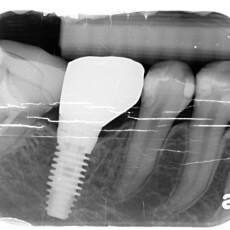

經由全口電腦斷層檢查,可以明確的知道植牙區骨頭的3D結構,從而了解您是否適合植牙,判斷根據可以參考植牙區需不需要補骨補肉

• 精準定位:診所備有目前全球頂級的德國KaVo電腦斷層,您不須再到影像中心拍攝,同時可以做到手術中拍攝定位,最佳化植體位置,避免植體位置不佳或是損害神經的風險.